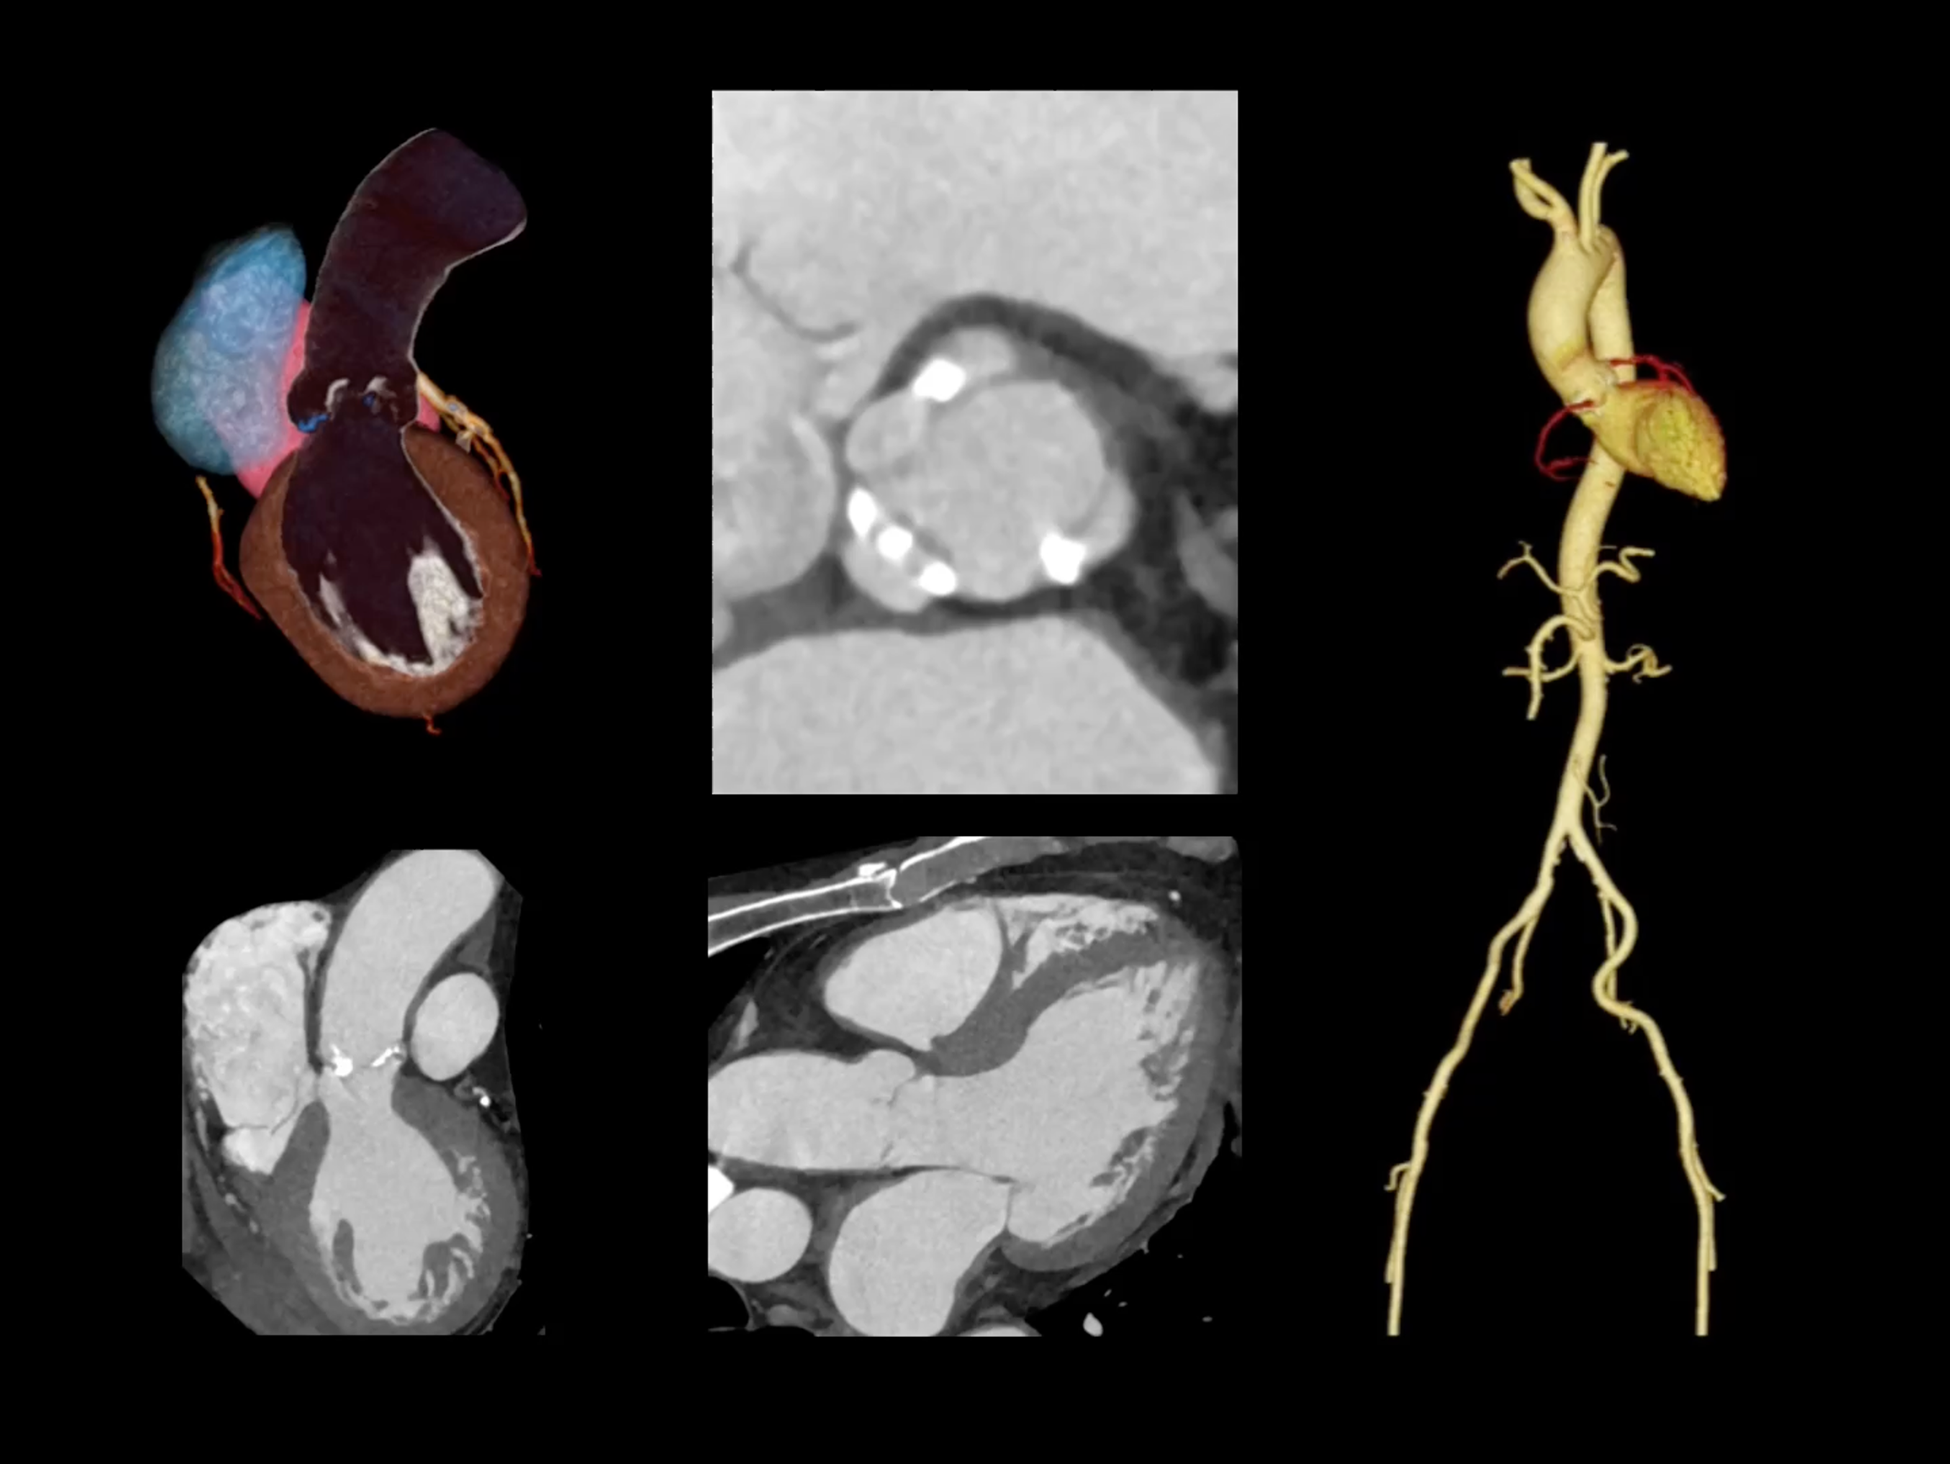

全时心脏

uCT SiriuX® 挑战心脏成像时间分辨率的极限,精准捕捉心脏全周期的动态变化。无论静态解剖形态,还是动态功能表现,都能清晰呈现,让心脏不再是“定格”的器官,而成为可视的生命律动。

心脏成像,自由掌控

uCT SiriuX® 以 8ms 全心等效时间分辨率与16cm宽体覆盖,突破传统心脏成像局限,完整呈现搏动中的心脏结构与动态功能;配合无心电门控扫描与智能化工作流,更使心脏检查摆脱心率、配合度与操作复杂度的束缚,实现真正自由从容的成像体验,为临床功能评估提供更深层依据。

全心4D电影成像

提供全心动周期内多个时相的清晰结构成像信息,动态展示心脏结构运动变化。

全心全时相高清成像

单心动周期内的任意时相获取高质量的冠脉CTA图像,确保稳定的心脏成像效果。

一站式心脏多维成像

一次对比剂注射可同时获取冠脉CTA、心肌灌注和心肌延迟强化等多维图像信息。